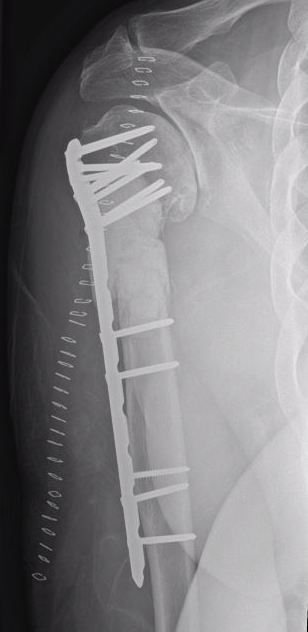

Orthopedic Management

1. To confirm diagnosis - biopsy isolated lesions

2. To treat impending or actual pathological fracture

3. Rarely to excise solitary lesions

4. Pathological Fracture